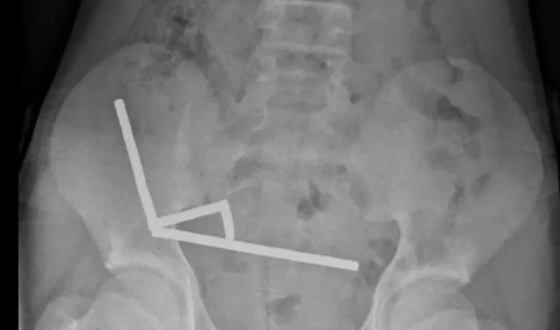

У Новій Зеландії 13-річному хлопчику довелося видалити близько 100 потужних магнітів, які він проковтнув після замовлення в інтернеті.